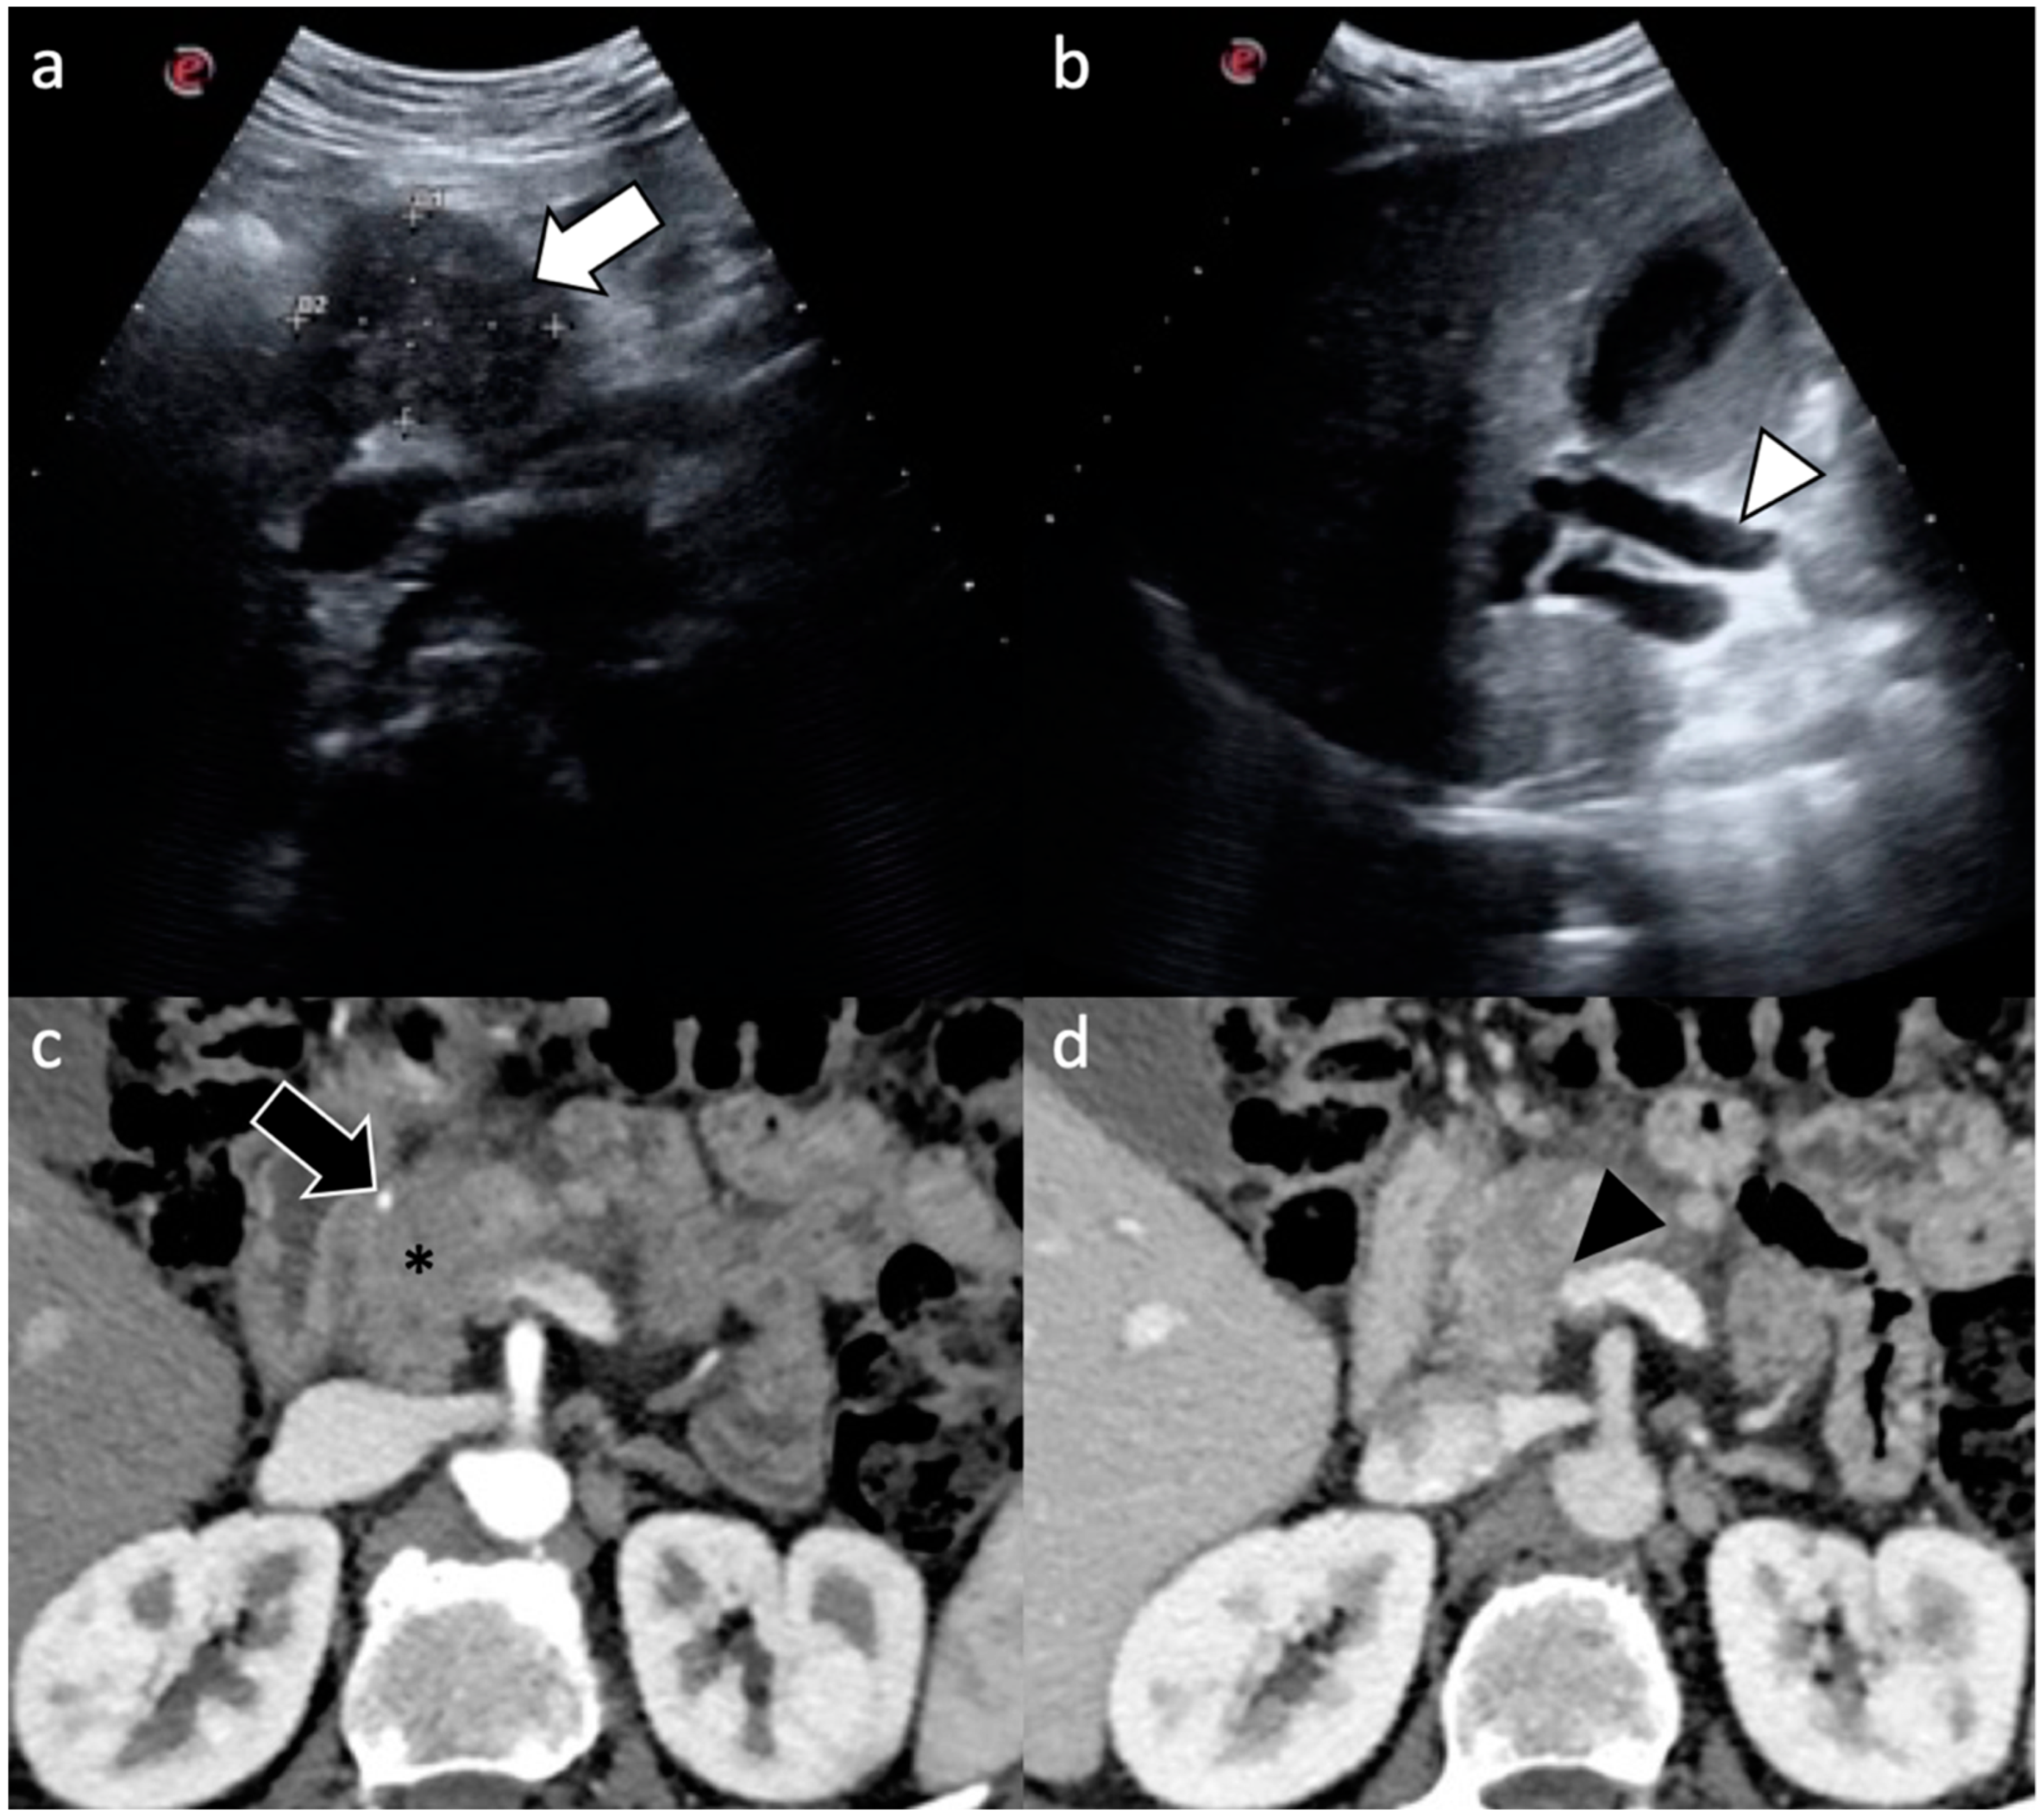

| Imaging Technique | Imaging Findings |

|---|---|

| Ultrasound |

|

| Computed Tomography |

| Magnetic Resonance Imaging |